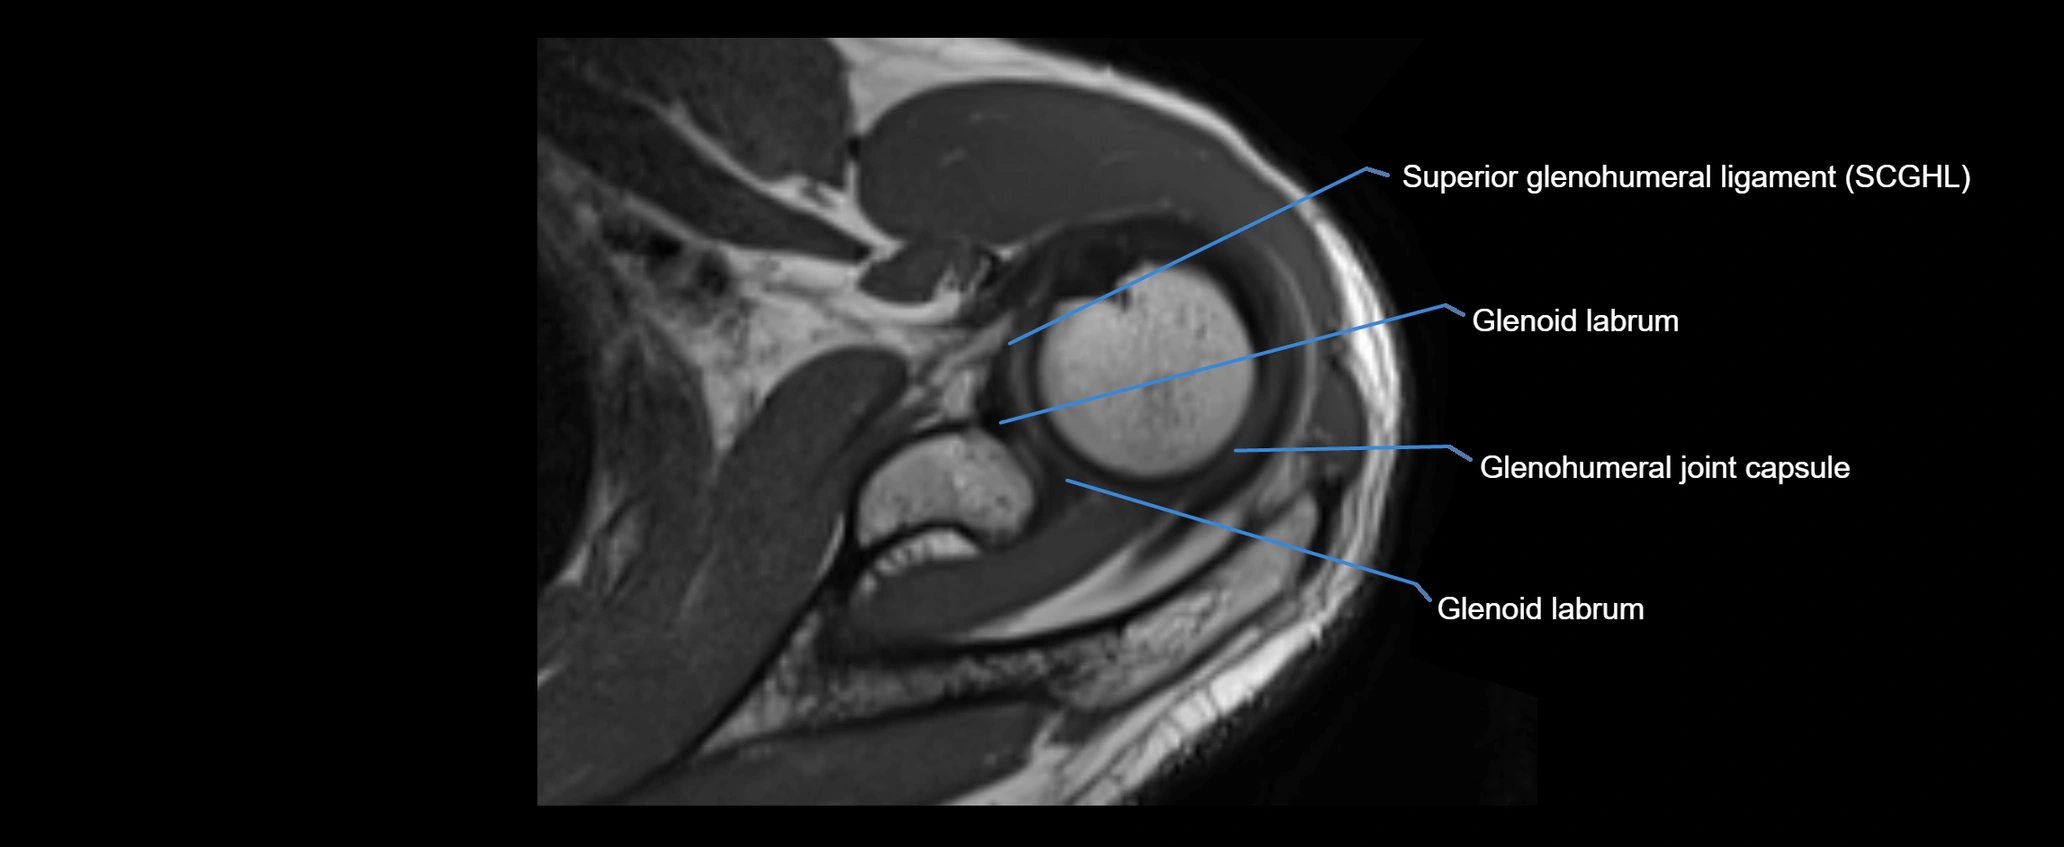

CT Appearance

Non-Contrast CT:

• Ligament: Not directly visualized due to small size and low density.

• Bony landmarks: Lateral clavicle and acromion clearly seen; cortical margins well defined.

• Pathology: Detects fractures, joint subluxation, osteophytes, and degenerative changes.

• Alignment assessment: Evaluates AC joint spacing and clavicular displacement.

CT image

image